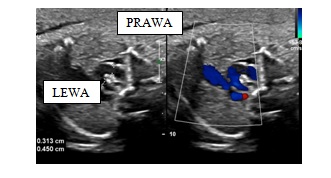

Zaniepokojony lekarz położnik prosi o konsultację obrazu śródpiersia płodu w 30 tygodniu ciąży podejrzewając przełożenie wielkich pni tętniczych. Pokazuje całe badania, w którym widoczne jest skrzyżowanie wielkich pni tętniczych, pień płucny wyraźnie odchodzi od przodu, ale aorta również się rozgałęzia. W obrazie czterech jam serca aorta piersiowa położona jest po prawej stronie kręgosłupa. Obraz śródpiersia widoczny jest na obrazie poniżej. Prawidłowe rozpoznanie i postępowanie to:

1) przełożenie wielkich pni tętniczych;

2) podwójny łuk aorty z porównywalną średnicą obu łuków;

3) prawostronny łuk aorty;

4) obraz śródpiersia u płodu jest prawidłowy;

5) noworodek powinien urodzić się w ośrodku z możliwością diagnostyki kardiologicznej.

Prawidłowa odpowiedź to: